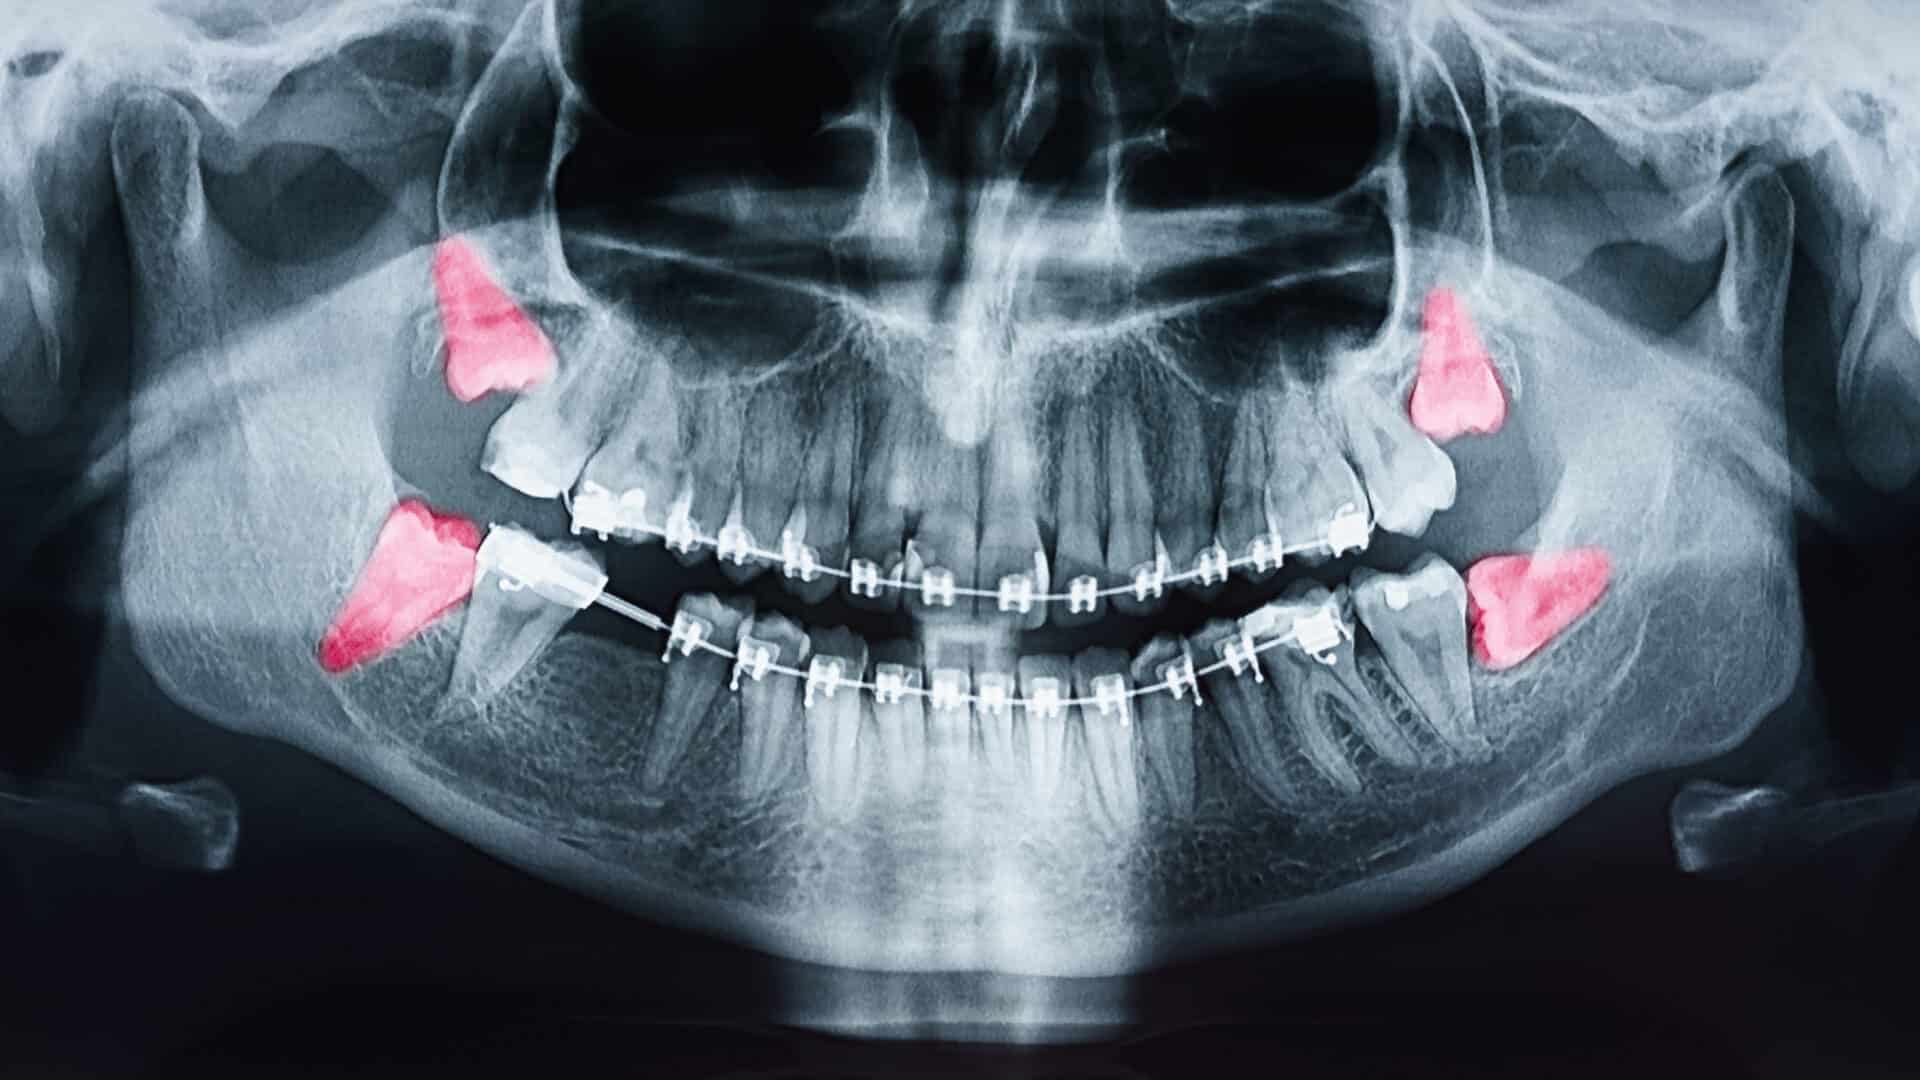

Sự sai lệch này dẫn đến áp lực bất thường trong quá trình mọc răng, khiến răng khôn đâm vào răng số 7 hoặc mọc ngầm trong xương. Nếu không phát hiện sớm, nó có thể gây đau răng khôn, viêm nướu và tiêu xương cục bộ. Việc chẩn đoán hình thể xương hàm bằng phim X-quang toàn cảnh giúp bác sĩ xác định chính xác hướng mọc để lên kế hoạch điều trị răng khôn mọc lệch phù hợp.

Tình trạng này thường gây đau răng khôn tái phát do mô nướu bị viêm nhiễm và áp lực giữa các răng tăng cao. Để điều trị răng khôn mọc lệch hiệu quả, bác sĩ cần đánh giá tương quan giữa các răng cối và hình dạng xương hàm thông qua phim Cone Beam CT 3D, từ đó xác định hướng phẫu thuật an toàn và ít sang chấn nhất.

Chẩn đoán chính xác là yếu tố tiên quyết trong điều trị răng khôn mọc lệch. Bác sĩ thường chỉ định chụp phim X-quang Panorama hoặc Cone Beam CT 3D để xác định hướng mọc, độ sâu, khoảng cách đến ống thần kinh và mức độ tiêu xương. Việc đánh giá lâm sàng kèm hình ảnh giúp tiên lượng mức độ khó và chọn phương pháp phẫu thuật phù hợp.